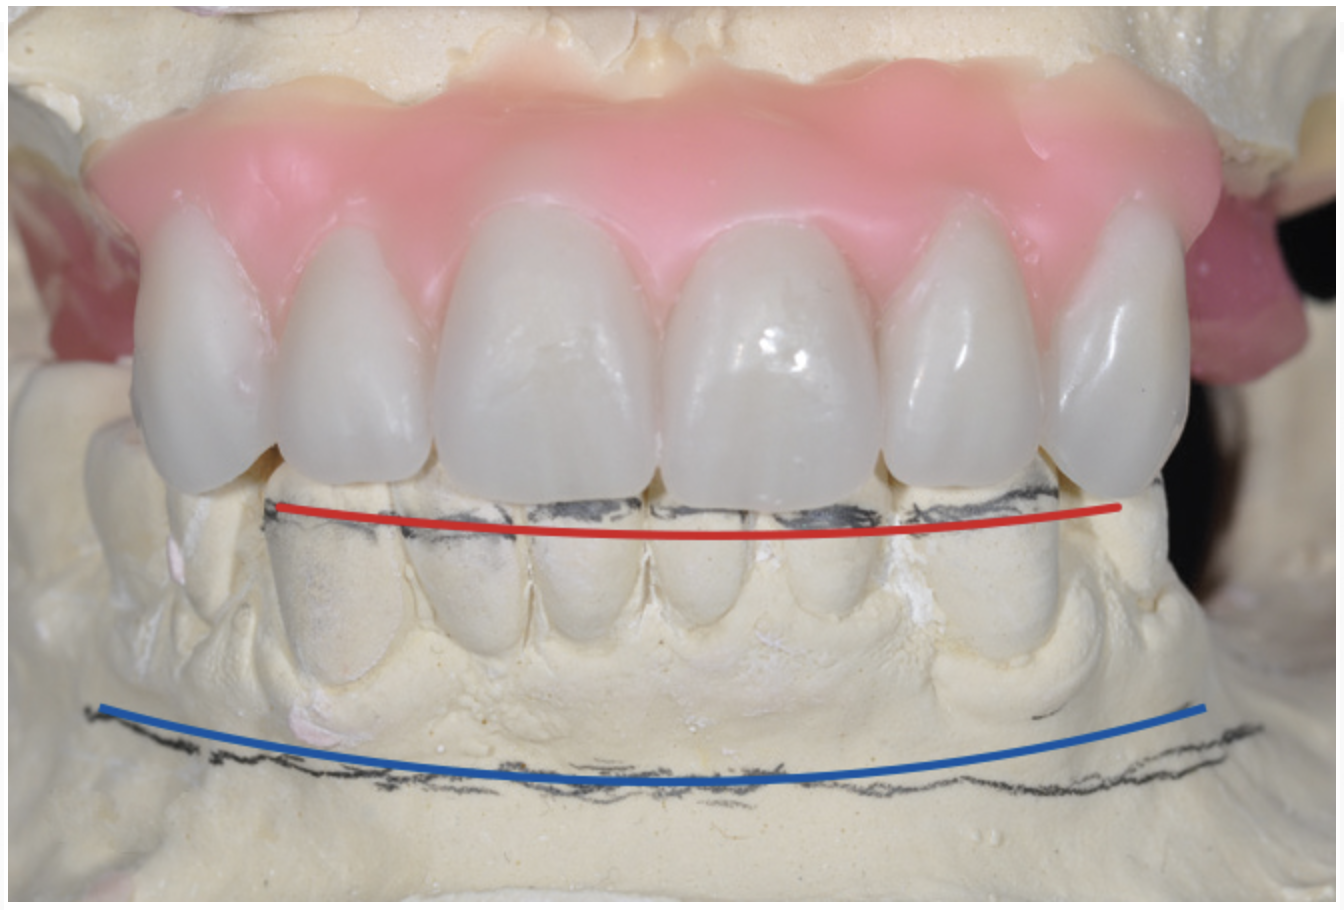

Model-Based Diagnosis and Treatment Planning

The authors’ All-on-4 treatment planning protocol relies on conventional diagnostic records, including mounted study models. When a single arch will be rehabilitated without changes to the incisal plane, occlusal plane, or the occlusal scheme of the opposing arch, diagnostic models are mounted on a hinge articulator with the aid of a bite registration. However, whenever changes to the incisal plane, occlusal plane, or occlusal scheme of the opposing arch are indicated or when skeletal inter-arch discrepancies require correction, diagnostic study models are mounted in duplicate on an adjustable articulator at the patient’s VDO aided by a facebow transfer and bite registration. When combined with clinical information gained from pre-treatment patient evaluations, all of the information required for interdisciplinary treatment planning is available.

An important advantage of this approach is the ability to simulate bone reduction on the models and verify the presence of 15 mm to 17 mm and 13 mm to 15 mm of required inter-occlusal space for maxillary and mandibular restorations, respectively. This creates a platform for a diagnostic wax-up of the proposed dental rehabilitation and fabrication of wax prosthesis try-ins when necessary. Finally, a modified All-on-4 provisional prosthesis surgical and restorative guide developed by the authors for restoration-driven surgery and simplified restorative procedures is fabricated (Figure 2 through Figure 8).

Fig 3. Desired changes in the incisal plane are marked on the diagnostic models.

Figure 3

Fig 4. Diagnostic wax-up performed after model surgery simulating maxillary tooth extraction. Note that inferior repositioning of the incisal plane helped create the 15 mm to 17 mm inter-occlusal space needed for the maxillary All-on-4 provisional restoration.

Figure 4

Fig 5. Bone reduction model surgery performed in mandibular arch to create 13 mm to 15 mm of inter-occlusal space required for the mandibular All-on-4 provisional restoration.

Figure 5

Fig 6. Completed diagnostic wax-up for maxillary and mandibular All-on-4 full-arch rehabilitation.

Figure 6